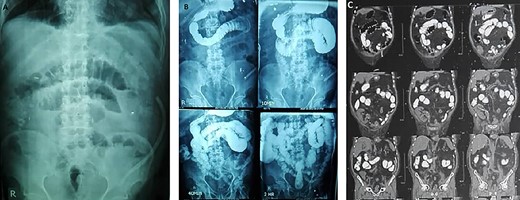

The patient was discharged 10 days following surgery. Post-operative period was uneventful and the only complication was ileus that improved with conservative management (Fig. 4). Serum creatinine was 1.2 (GFR = 65 ml/min/1.73m2) 3 months following surgery, with no evidence of recurrence during this short follow-up period.

Post-operative ileus is obvious in KUB (A), fluroscopic barium study (B) and abdomino-pelvic CT scan with oral contrast (C).